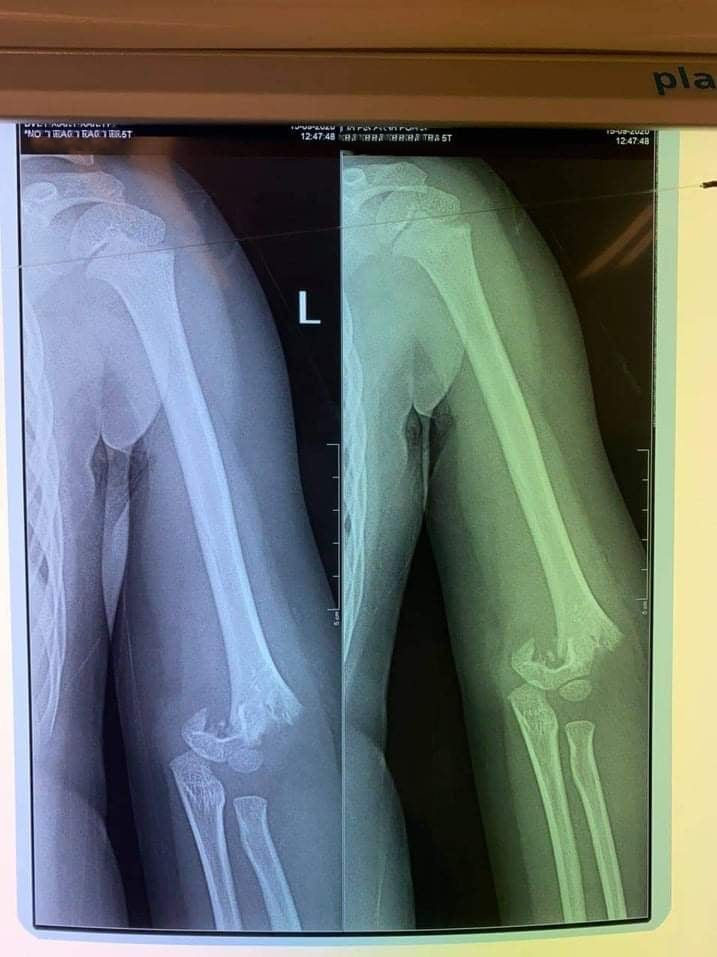

Sở GD&ĐT Hà Nội yêu cầu xác minh vụ trẻ mầm non bị gãy tay trong trường học ​ ảnh 1Hình ảnh chụp phim cho thấy trẻ bị gãy xương cánh tay.

Trước đó, một phụ huynh có con đi học ở Trường mầm non Vườn trẻ thơ, quận Hai Bà Trưng thông tin, trong giờ học ngoài trời, con bị bạn xô ngã dẫn đến gãy tay. Khi nhà trường đưa con đến viện chụp chiếu, tay con bị gãy phải mổ. Sự việc xảy ra cách đây khoảng chục ngày nhưng gia đình bận chăm sóc con đến nay mới thông tin sự việc.